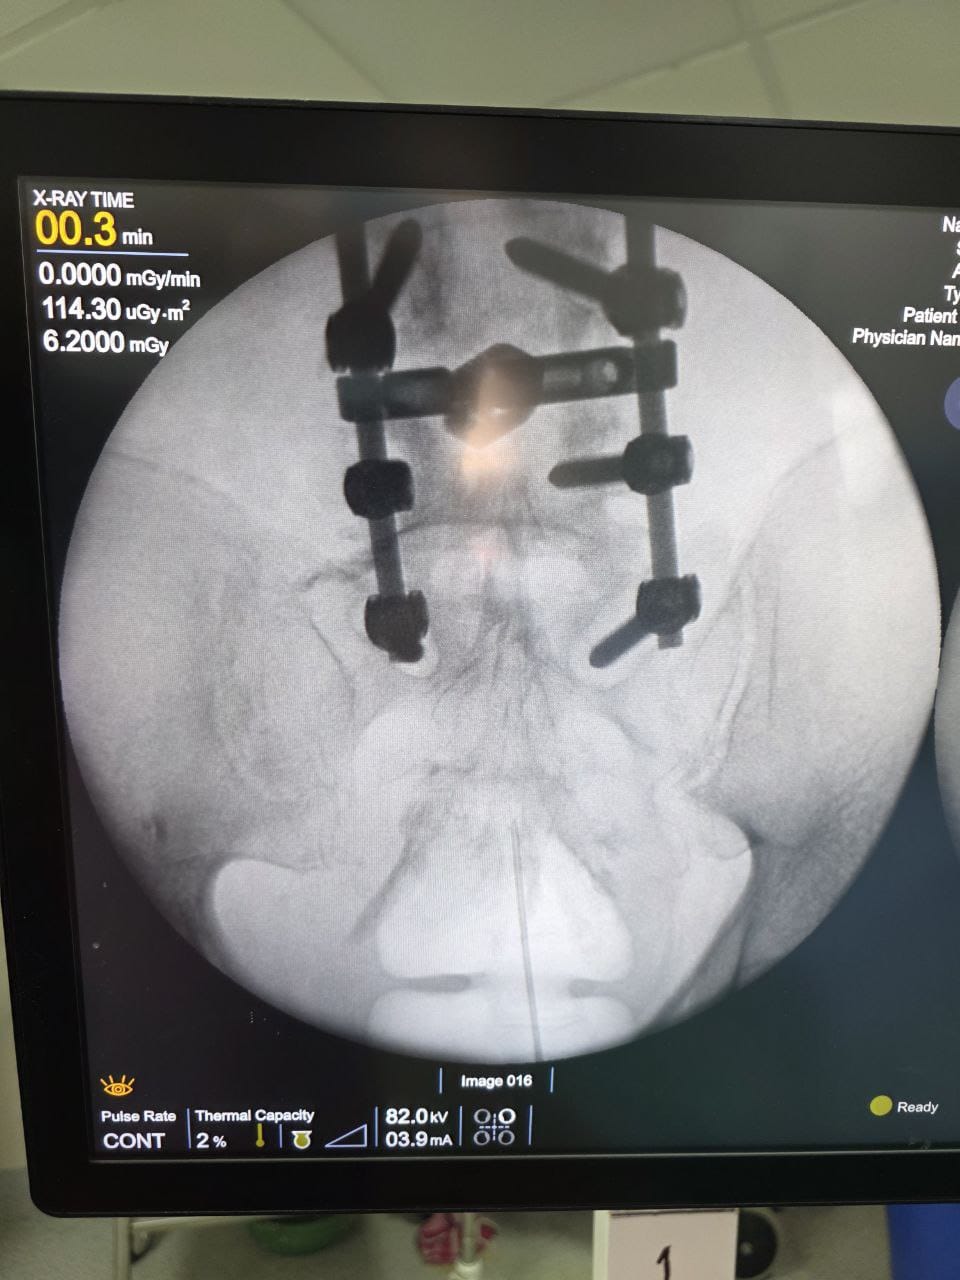

Procedures